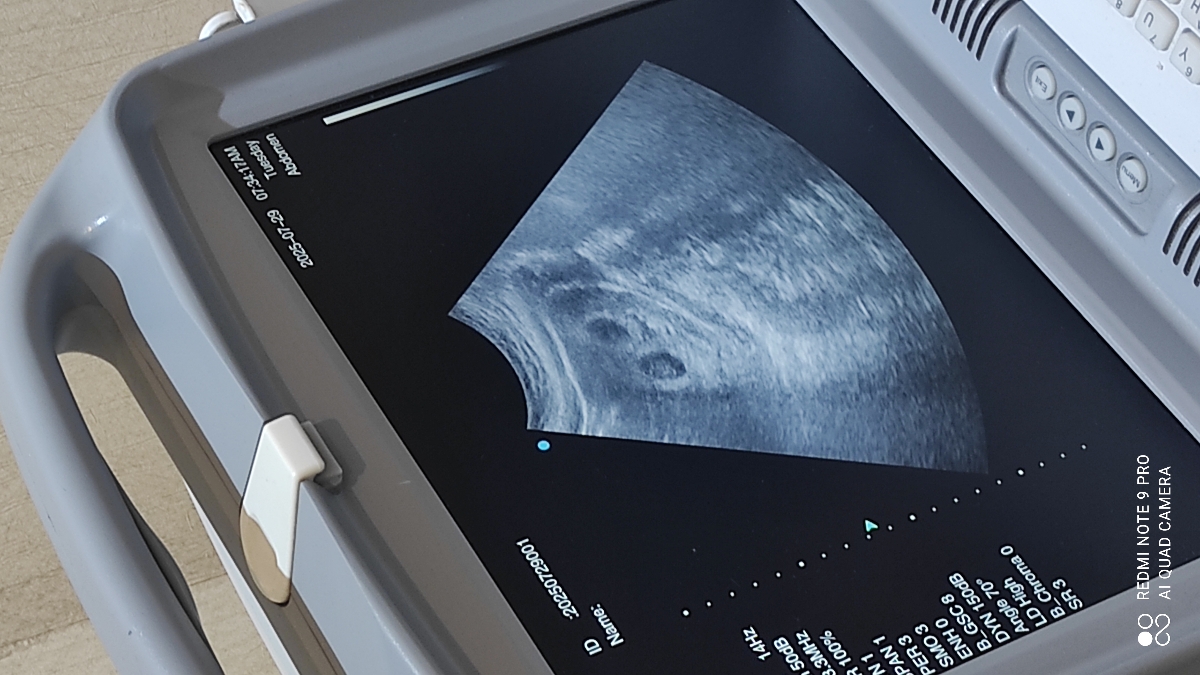

بنده ۷ هفته و ۵روزام هست و بارداری دو قلویی در دو کیسه جدا دارم

بله قلبشون تشکیل شده

این بود